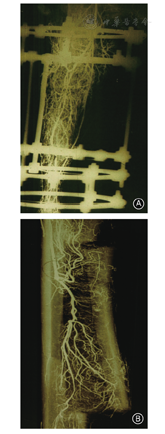

早在1956年Bost等[12]就提出的应用髓内钉进行骨延长的理念,Paley在1990年开始应用髓内针进行肢体延长手术(lengthening over nail,LON),并于1997年发表文献报告[13]。这种方法可以使骨延长维持更好轴线,大大缩短外固定佩戴的时间。完全植入式髓内钉肢体延长首次由乌克兰Bliskunov报告[14],在1990年Guichet[15]研制了Albizzia自行延长钉,几乎在同一时间Baumgart[16]和Betz研制了Fitbone机械钉。1994年Dean Cole研制的ISKD[17]是第一个美国FDA批准的完全植入肢体延长髓内钉,2011年Ellipse的Precice是第二个FDA批准的髓内延长器械[18]。可延长髓内钉(图4)的出现是肢体延长史上的重大突破,因其美观舒适,加之器械和技术不断升级,在越来越多的国家和地区应用,在一定程度上正逐渐取代外固定肢体延长。